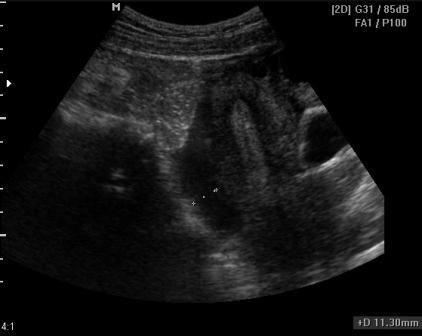

Через день после 1-го УЗИ и после проведения кульдоцентеза, в результате которого было получено примерно 160мл "ржавой жидкости, в малом тазу вот такая картина:

Из того, что понятно: есть киста хвоста поджелудочной железы, жидкость в малом тазу (мелкодисперстная) и немного в брюшной полости (с нитями фибрина), кисты правого яичника.

P.S.:Результат повторного кульдоцентеза: амилаза 817, эритроциты в большом количестве.

Геморрагическая жидкость характерна для о.панкреатита.